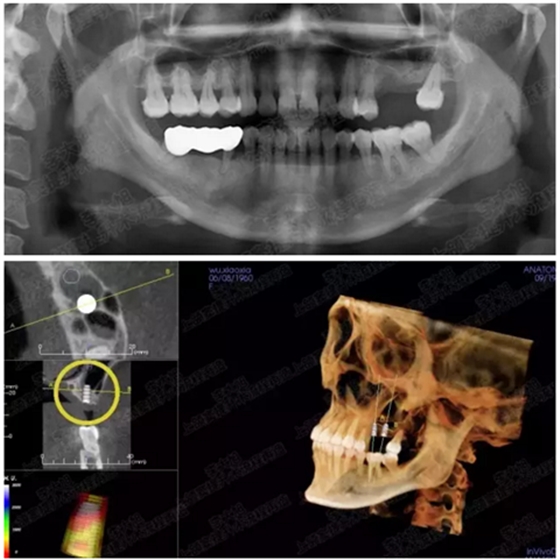

病例二

剩余骨量2mm

003.png

提升10mm

004.png